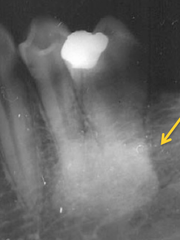

Radiolucent and radiopaque (radiographic terms used to describe lesions in bone)

Front

Terms used to describe a mixture of light and dark areas within a lesion, usually denoting a stage in the development of the lesion; for example in a stage I periapical cemento-osseous dysplasia (cementoma) the lesion is radiolucent; in stage II it is radiolucent and radiopaque.